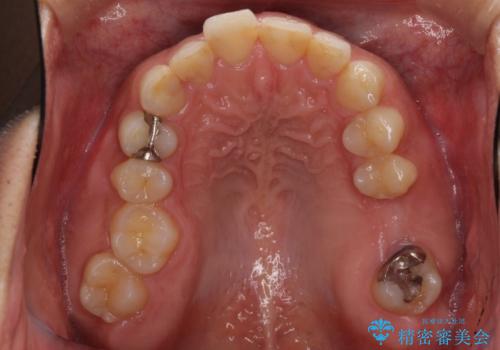

- 深い咬み合わせと前歯のデコボコ、奥歯の欠損を気にして来院された患者様です。

歯列矯正はインビザラインを使用し、矯正治療中の適切な時期に奥歯の欠損部位にインプラントを埋入することとしました。